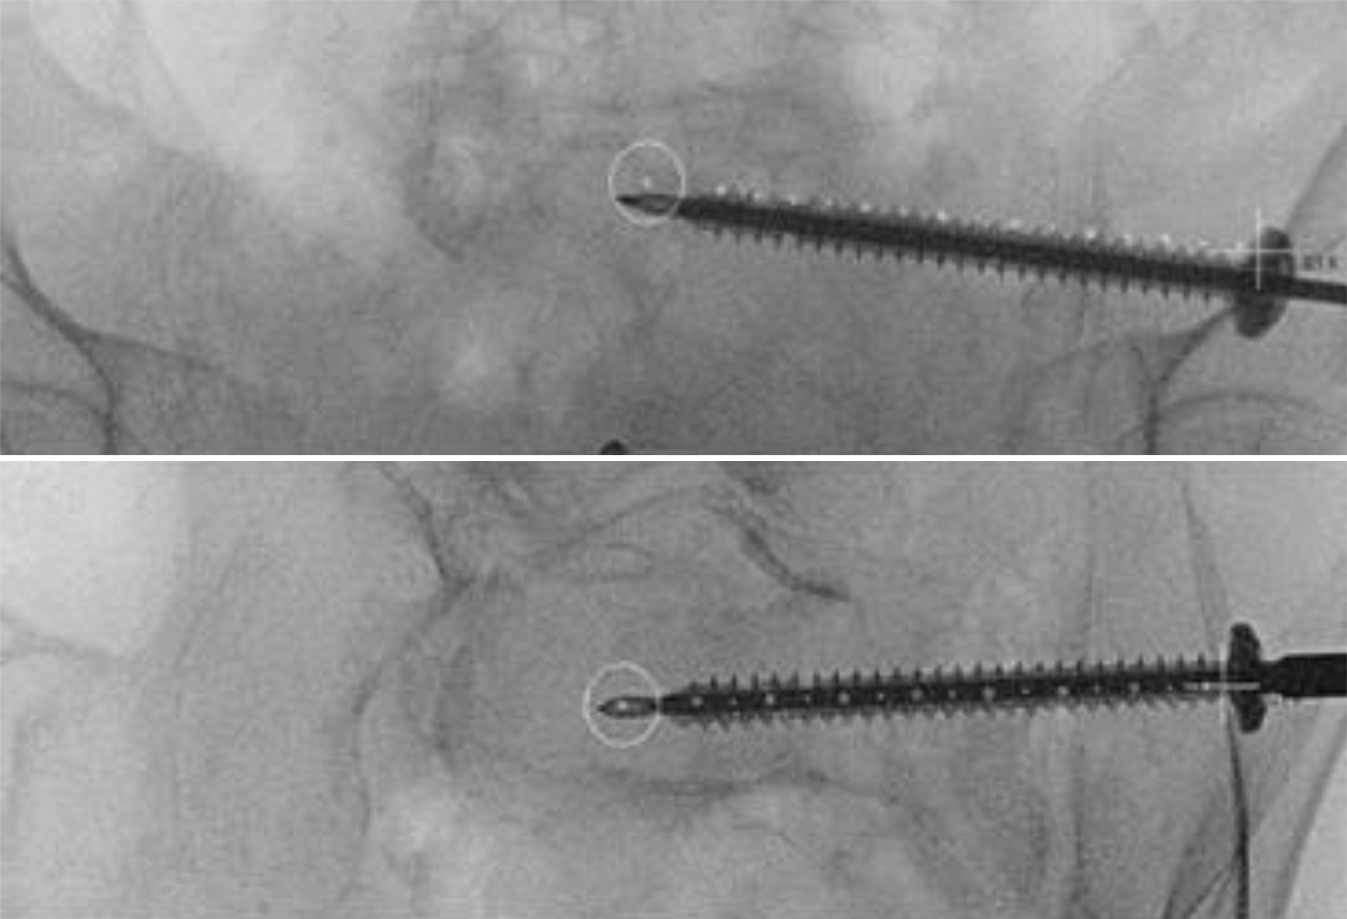

Fig. 8

a Measurement of the intended screw length. b The guidewire is over drilled through three cortices with a 5.0 mm drill into the sacrum. Due to the osteoporotic bone, it is not necessary to over-drill the entire length of the guidewire. c A cannulated screw is manually inserted over the guidewire; a washer is utilized to prevent intrusion into the ilium. Correct snug positioning of the washer on the cortex is checked with an x‑ray in 20° ipsilateral tilt

Fig. 9

At this stage, a 3D scan can be performed to verify the screws’ correct positioning. In our department, 3D scans are typically conducted at the end of the procedure. For introducing a second screw on the contralateral side, a mirrored version of the original lateral view is used to identify the correct entry point